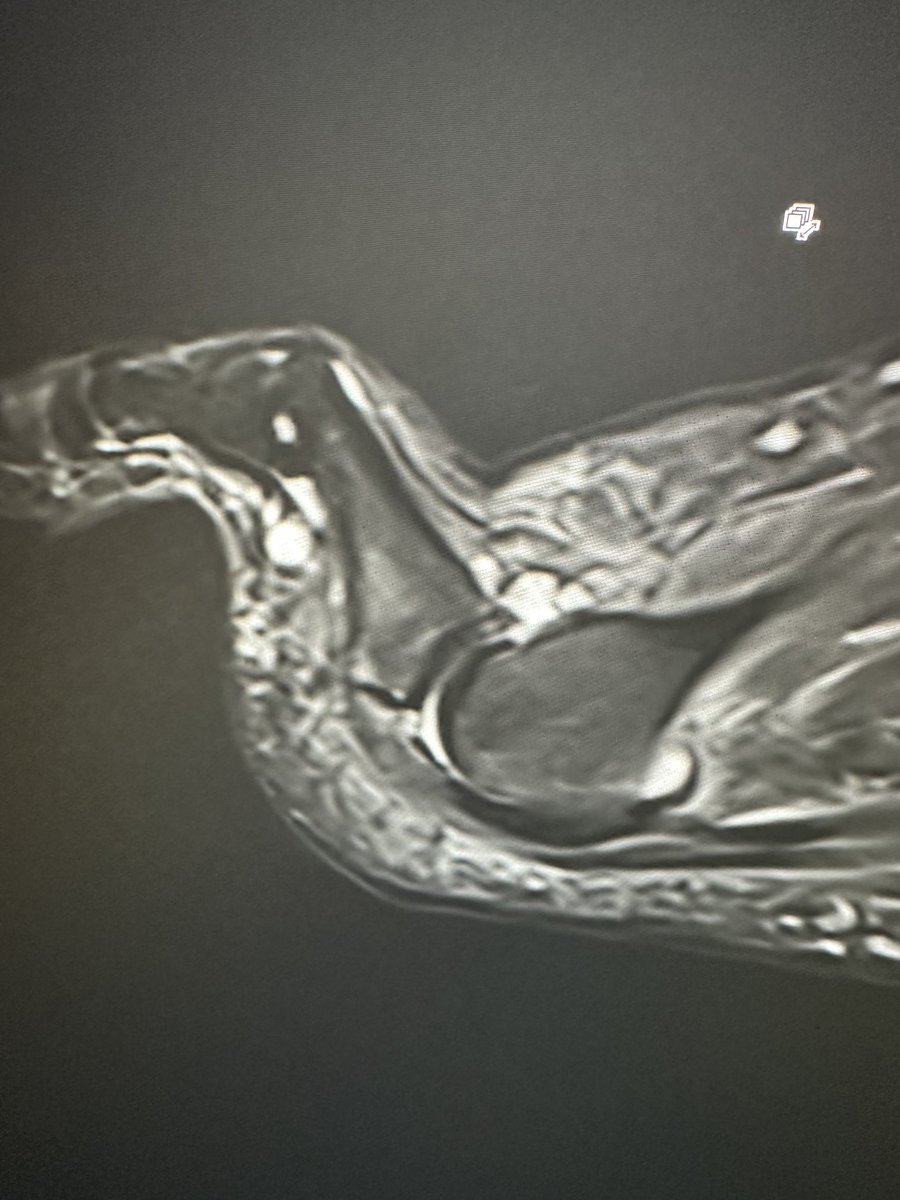

Update - L radicular leg pain & foot drop almost resolved Unfortunately symptoms evolved to become bilateral gluteal, pelvic & groin - 2 weeks ago When the pain got to 9-10/10 & I couldn't sleep / walk, I decided to forego watching the Hungarian Grand Prix & head to Urgent Care at PGH instead - raised CRP & neutrophilia MRI on Sunday at Fortius (amazing service) - raging bacterial disciitis & epidural abscess Don't tell anyone but it's affecting the psoas so I can't SLR 😆 So now in hospital awaiting PICC line and 2-3 months antibiotics 😕❎

James Noake tweet mediaJames Noake tweet mediaJames Noake tweet media

Update for those interested! 16 days post discectomy Minimal pain - low grade 2/10 neural ache buttock and fibula head / shin Worse at night and morning but variable Numbness is more annoying! Tib ant power recovering Doing simple upper body weights typically seated or cable Iso rehab for quad, hamstrings and tib ant Stationary bike & elliptical trainer - easy steady state I’m behaving and listening to my brilliant physio Chris Whittle @puresportsmed